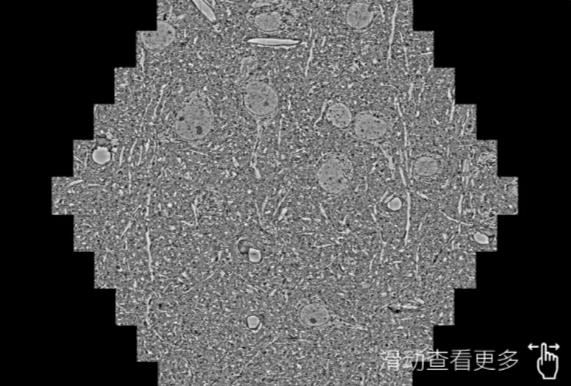

鼠脑切片。左图使用淮南蔡司淮南扫描电镜MultiSEM706对165μmx143pm面积区域成像,耗时仅需1.5秒。右图为鼠脑切片中30μm区域放大效果。样品由芝加哥大学B.Kasthuri提供。

使用蔡司高速淮南扫描电镜MultiSEM对1mm²人脑皮层组织进行高分辨成像,并对其中的各种细胞结构进行三维重构分析。左图展示了2x3mm²组织平面中锥体神经元的三维重构效果。右图显示了局部体积神经元三维重构。图像由哈佛大学chtman实验室提供,渲染图由D. Berger 制作。